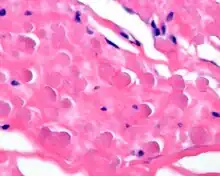

By microscopie view, there is an admixture of heavy dense bands of collagenous tissue dissected by fat and abnormal elastic fibers. The elastic fibers are often quite large and are easily identified. The elastic fibers are coarse, thick, and darkly eosinophilic, often fragmented into globules, creating a "string of pearls" or "pipe cleaner" appearance. Because of degeneration, the elastic fibers will appear as globules with a serrated or "prickled" edge.[5]